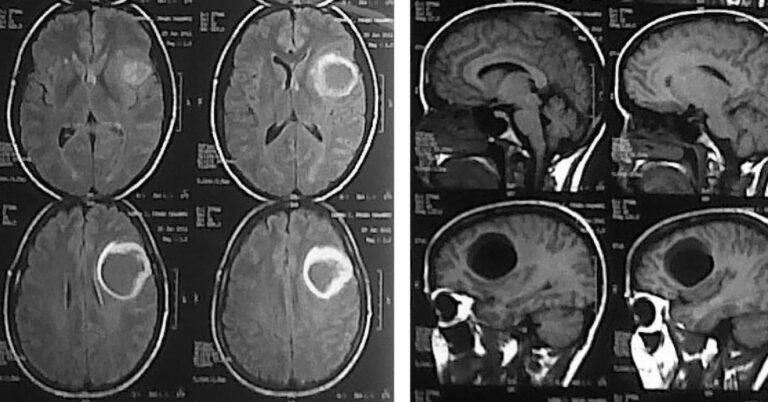

Tumor Cerebral

Vídeo com imagens de tumor cerebral fetal. O vídeo acima está publicado no YouTube e aqui você vê…